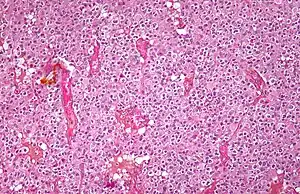

| Micrograph of an oligodendroglioma showing the characteristic branching, small, chicken wire-like blood vessels and fried egg-like cells, with clear cytoplasm and well-defined cell borders. H&E stain. | |

Oligodendrogliomas cannot currently be differentiated from other brain lesions solely by their clinical or radiographic appearance. As such, a brain biopsy is the only method of definitive diagnosis. Oligodendrogliomas recapitulate the appearance of the normal resident oligodendroglia of the brain. (Their name derives from the Greek roots 'oligo' meaning " few" and 'dendro' meaning "trees".) They are generally composed of cells with small to slightly enlarged round nuclei with dark, compact nuclei and a small amount of eosinophilic cytoplasm. They are often referred to as "fried egg" cells due to their histologic appearance. They appear as a monotonous population of mildly enlarged round cells infiltrating normal brain parenchyma and producing vague nodules. Although the tumor may appear to be vaguely circumscribed, it is by definition a diffusely infiltrating tumor.

Classically they tend to have a vasculature of finely branching capillaries that may take on a "chicken wire" appearance. When invading grey matter structures such as cortex, the neoplastic oligodendrocytes tend to cluster around neurons exhibiting a phenomenon referred to as "perineuronal satellitosis". Oligodendrogliomas may invade preferentially around vessels or under the pial surface of the brain.